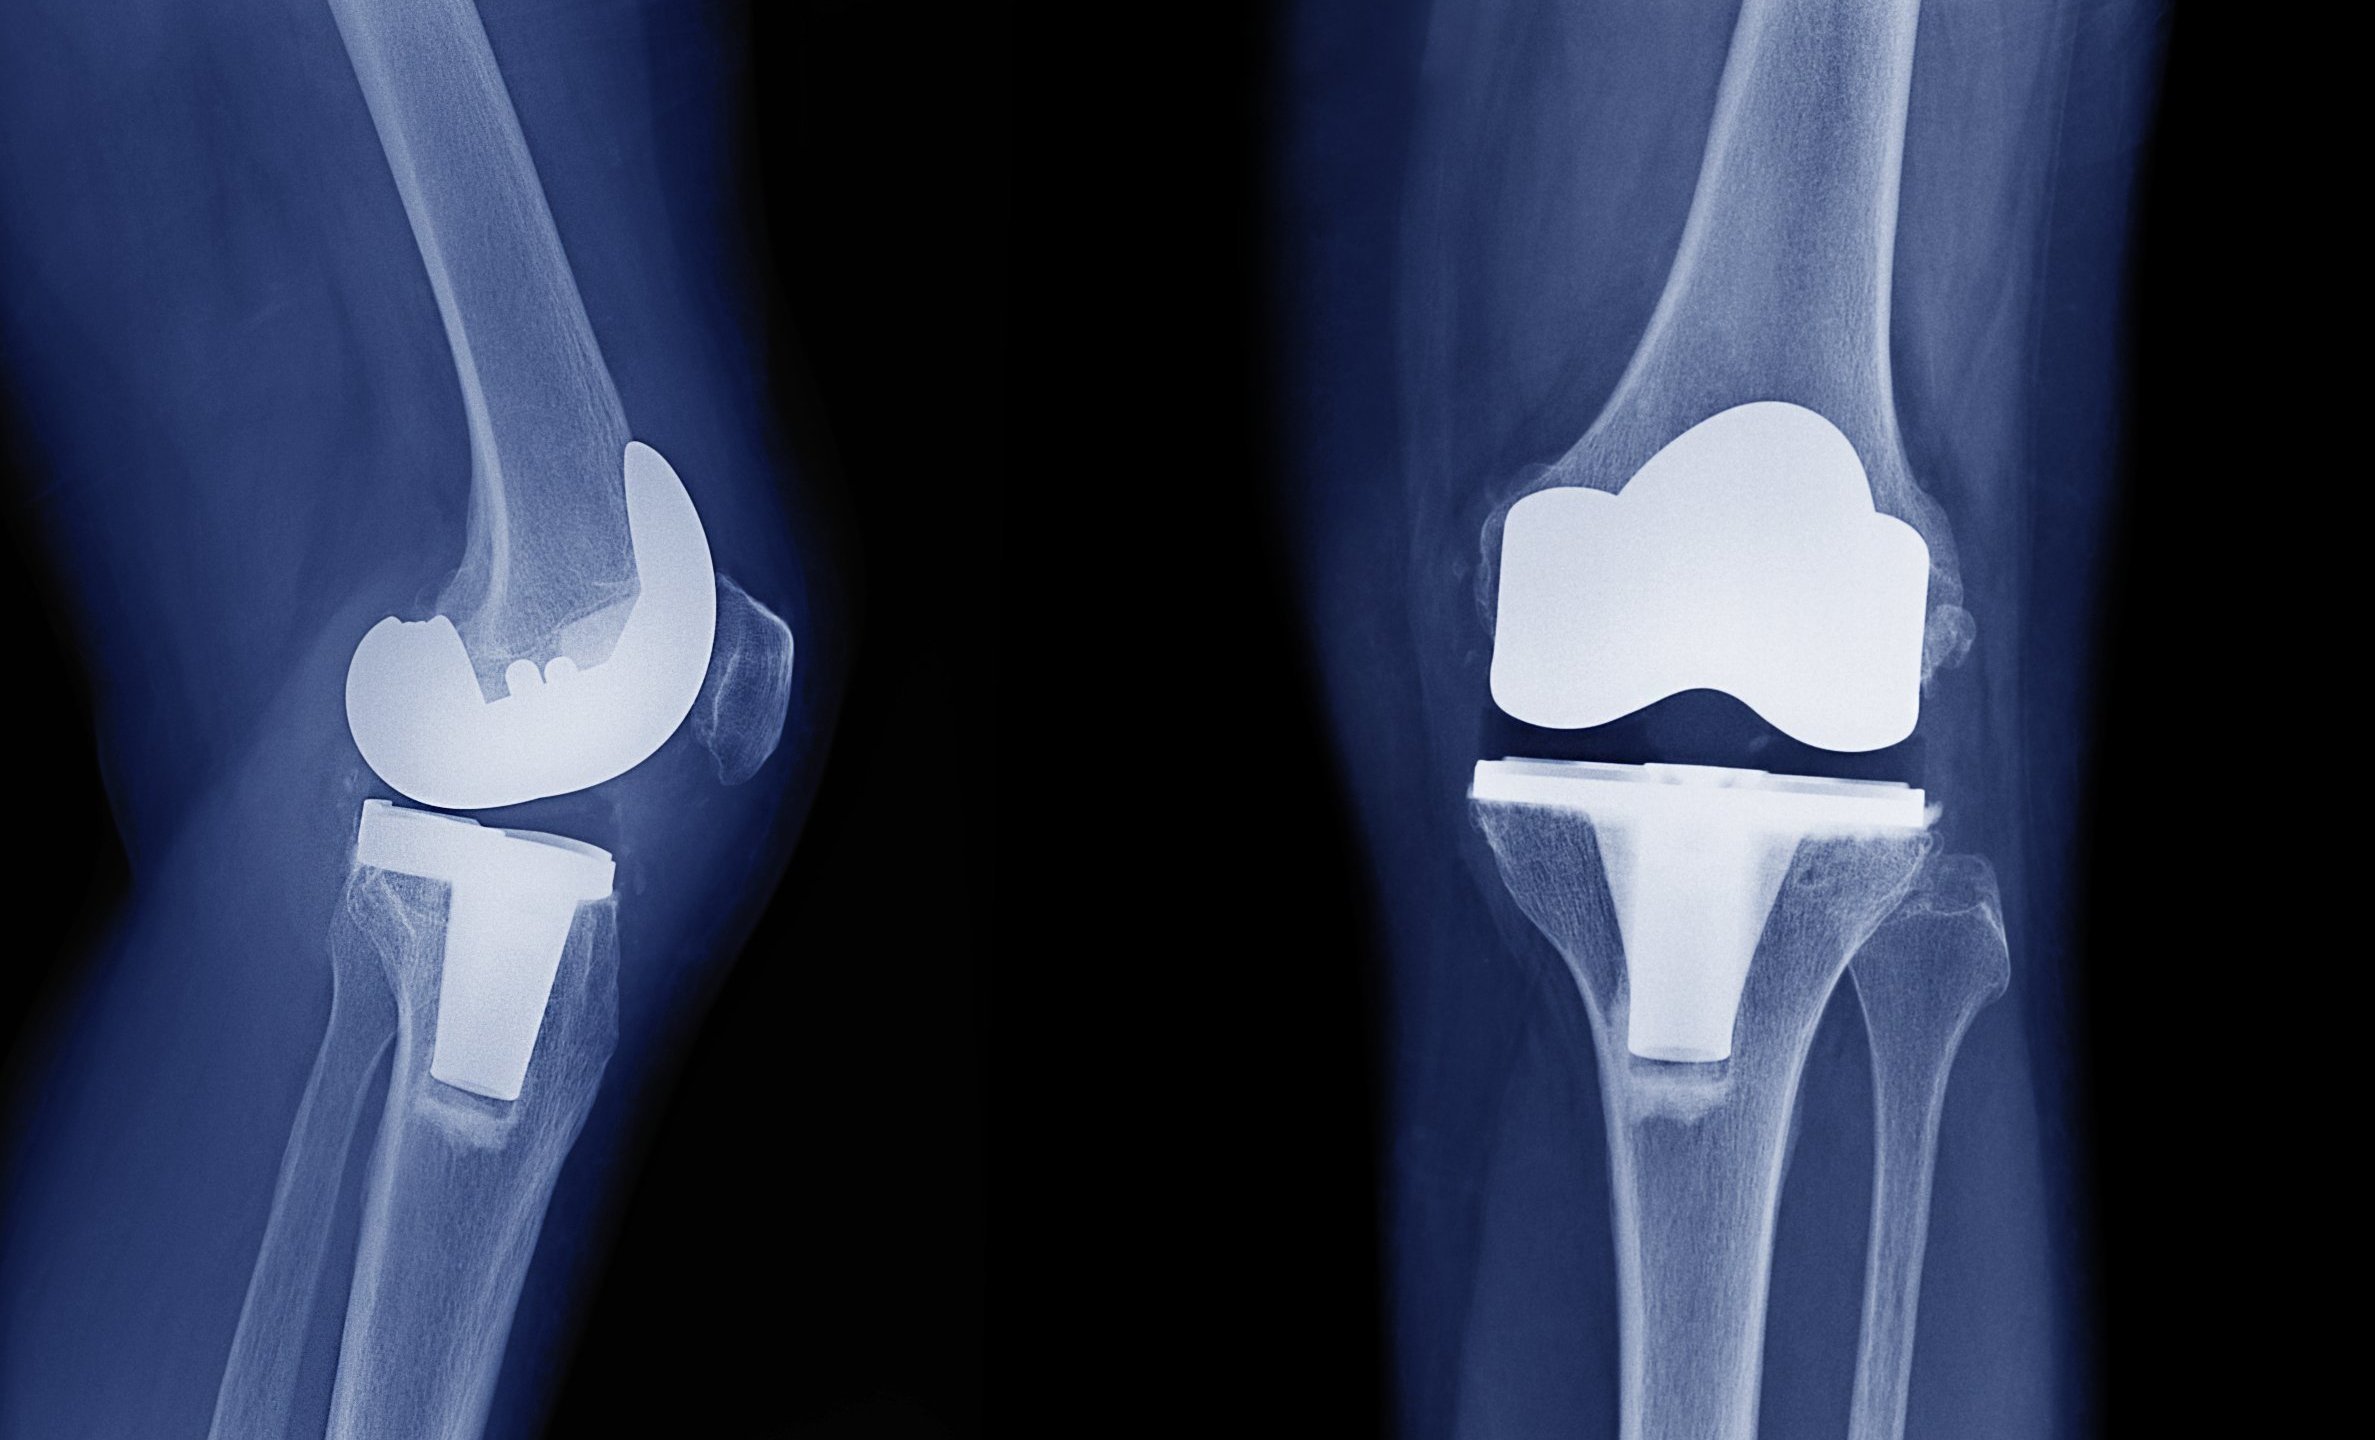

Knee replacement, also known as knee arthroplasty, is a surgical procedure that replaces the weight-bearing surfaces of the knee joint to relieve pain and disability. It is most commonly used when conservative measures fail to alleviate joint pain, as well as for other knee diseases like rheumatoid arthritis and psoriatic arthritis. The procedure may be more challenging and riskier in individuals with significant deformity caused by advanced rheumatoid arthritis, trauma, or long-term osteoarthritis. Osteoporosis does not usually cause discomfort, deformity, or inflammation in the knees, and it is not a rationale for knee replacement.

Knee replacement, also known as knee arthroplasty, is a surgical procedure that replaces the weight-bearing surfaces of the knee joint to relieve pain and disability. It is most commonly used when conservative measures fail to alleviate joint pain, as well as for other knee diseases like rheumatoid arthritis and psoriatic arthritis. The procedure may be more challenging and risky in individuals with significant deformity caused by advanced rheumatoid arthritis, trauma, or long-term osteoarthritis. Osteoporosis does not usually cause discomfort, deformity, or inflammation in the knees, and it is not a rationale for knee replacement.